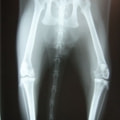

レントゲン検査

骨生検および病理組織検査

レントゲン検査所見から、骨もしくはその周囲組織に発生した腫瘍の可能性が考えられたため、病変部の細胞診検査およびジャムシディ生検針を用いた病変の骨生検を実施した。病理組織検査の結果、非上皮性の悪性腫瘍である“肉腫”と診断された。

内科治療に反応が乏しい四肢の跛行や疼痛は、本症例のように腫瘍が原因となっていることがあるため、レントゲン検査、骨生検等積極的に原因追及のための検査を実施することが必要である。骨の破壊を起こす悪性腫瘍は、非常に強い痛みを伴い、消炎鎮痛剤を用いても痛みを抑えることが困難となる。痛みの除去および腫瘍の治療のために断脚手術や抗がん剤等が必要となる場合があり、似た症状を示す整形外科疾患等とは治療法・予後が異なるため、その鑑別は重要である。